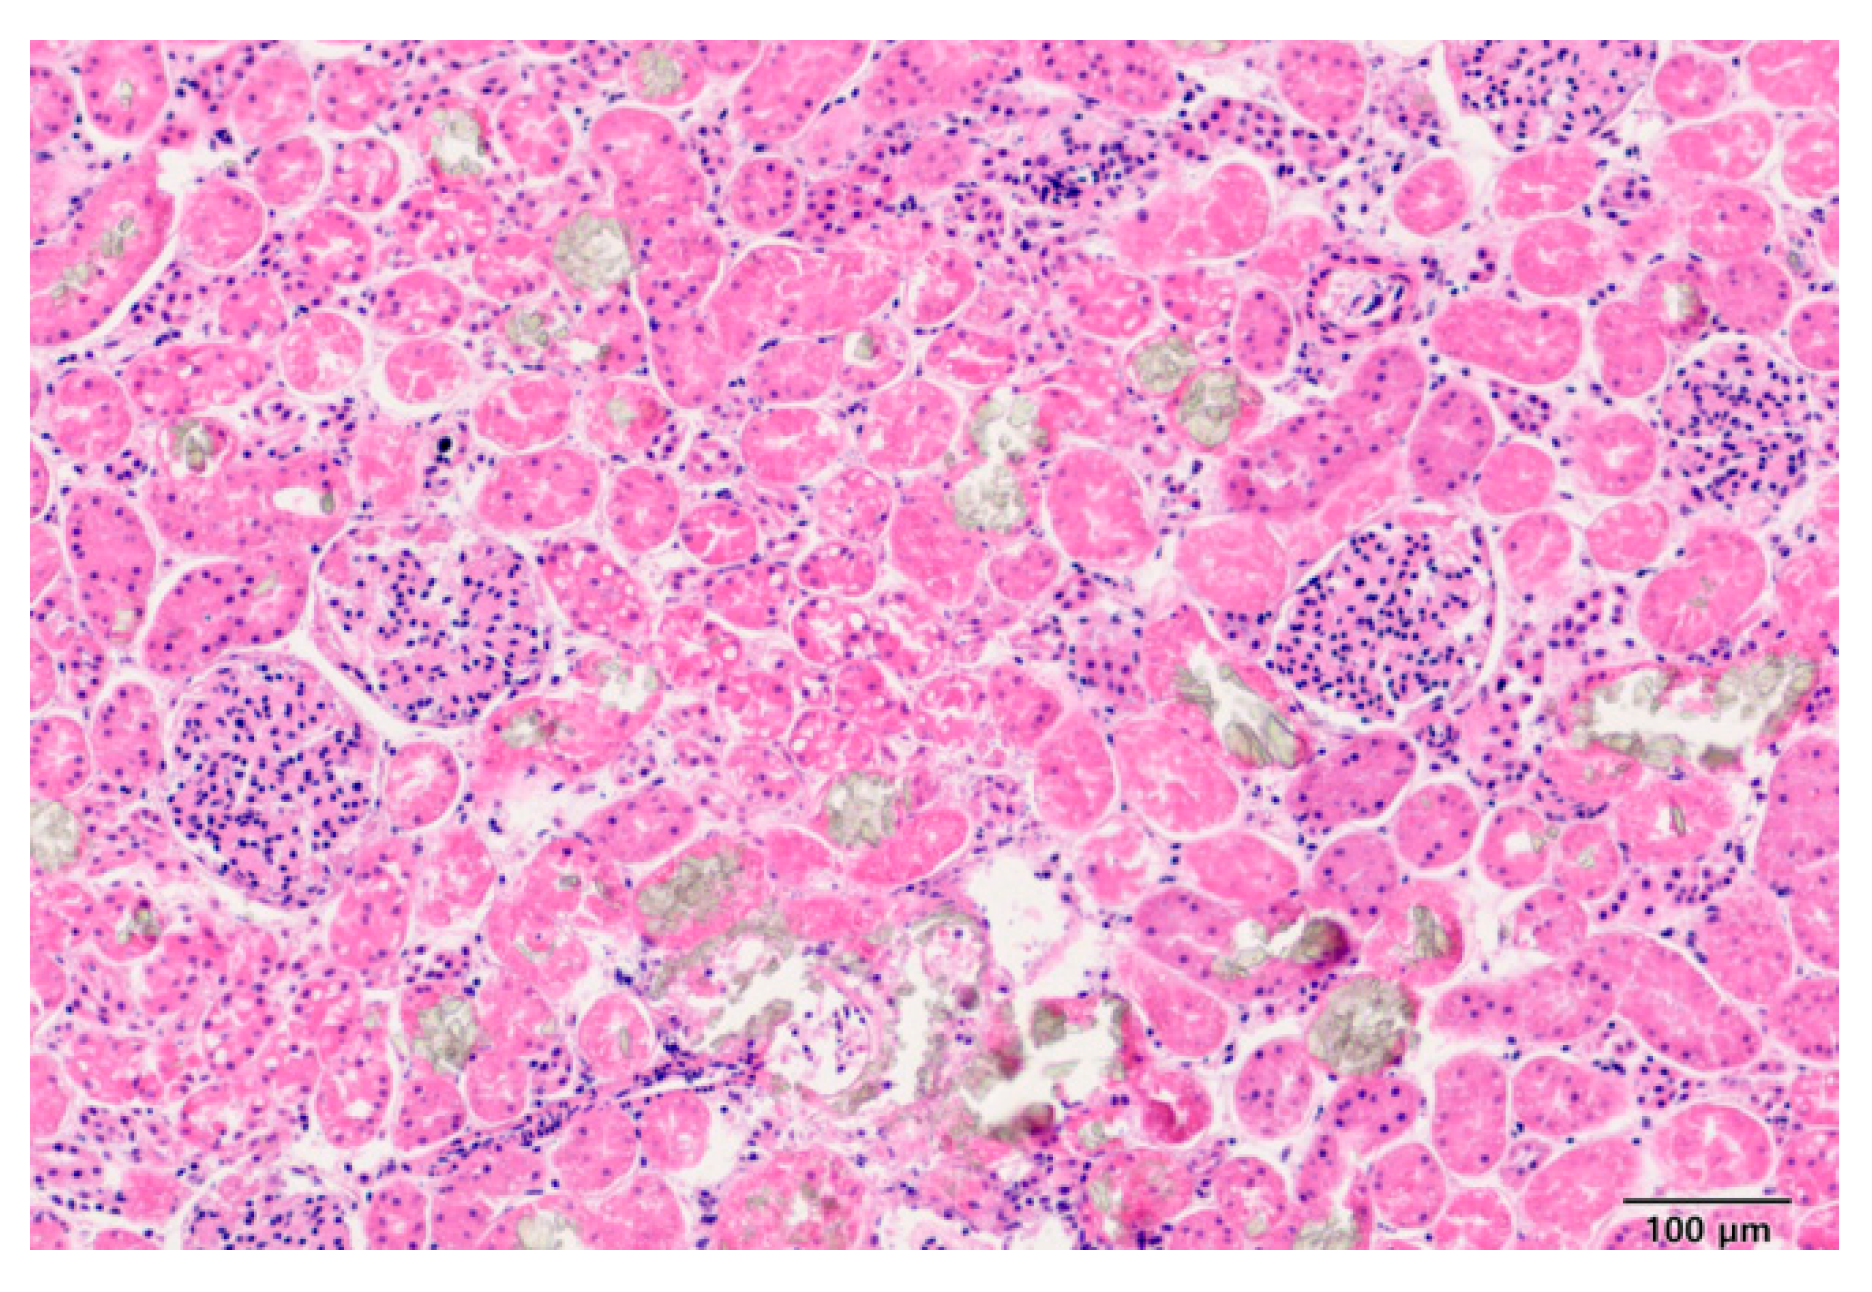

| Case 1 | EG | 82 | 69 | 67 | Organ bleeding, mild calcium oxalate crystals within the kidneys |

| Case2 | EG | 572 | 395 | 367 | Calcium oxalate crystals within the kidneys |

| Case3 | EG | 590 | 473 | 359 | Calcium oxalate crystals within the kidneys |

| Case4 | EG | 541 | 313 | 410 | Calcium oxalate crystals within the kidneys |

| Case5 | EG | 497 | 387 | 340 | Calcium oxalate crystals within the kidneys |